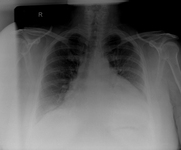

CXR in a patient with a pericardial effusion showing typical findings of a water-bottle-shaped cardiac silhouette with a distinct, fat, pericardial fat stripe

From the collection of Dr Rajdeep Khattar